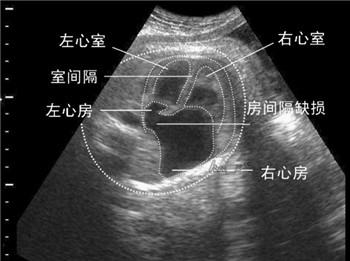

大千世界,无奇不有。最近,国外一个流浪孕妇在孕4月去医院产检时不幸发现胎儿心脏有缺陷,考虑到自己贫穷和居无定所,她痛苦地决定结束胎儿的生命。

谁也没用想到,她停止服药后,腹中的宝宝竟然茁壮成长,直到宝宝分娩,医护人员的检查结果让她简直不敢相信自己的眼睛,孩子非常完美健康,没有一点疾病,孕期检查出来的心脏缺陷和主动脉弓发育不全竟然“自我矫正”,不知什么时候不知不觉自愈了!医生也无法做出科学解释,只是说宝宝的心脏可能经历自我修复,他真的是个奇迹宝贝,是上帝送给流浪孕妇的礼物。

如果只是患有简单的先心病,出生后通过治疗是可以完全治愈的,还甚至出现某些胎儿母体内自愈的情况,但这类情况甚少见;宫内被确认的严重心血管病的胎儿,能够长期存活的极少。所以最好的还是孕期妈妈注意预防,注意饮食和及时产检。所以胎儿心脏有问题是否要流掉,最好征求医生专业意见。